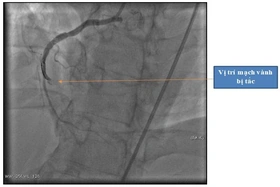

baophutho.vn Bệnh viện Đa khoa tỉnh vừa cấp cứu người bệnh đột ngột bị ngừng tim, các bác sĩ và điều dưỡng đã thay nhau ép tim liên tục gần 2 giờ đồng hồ,...